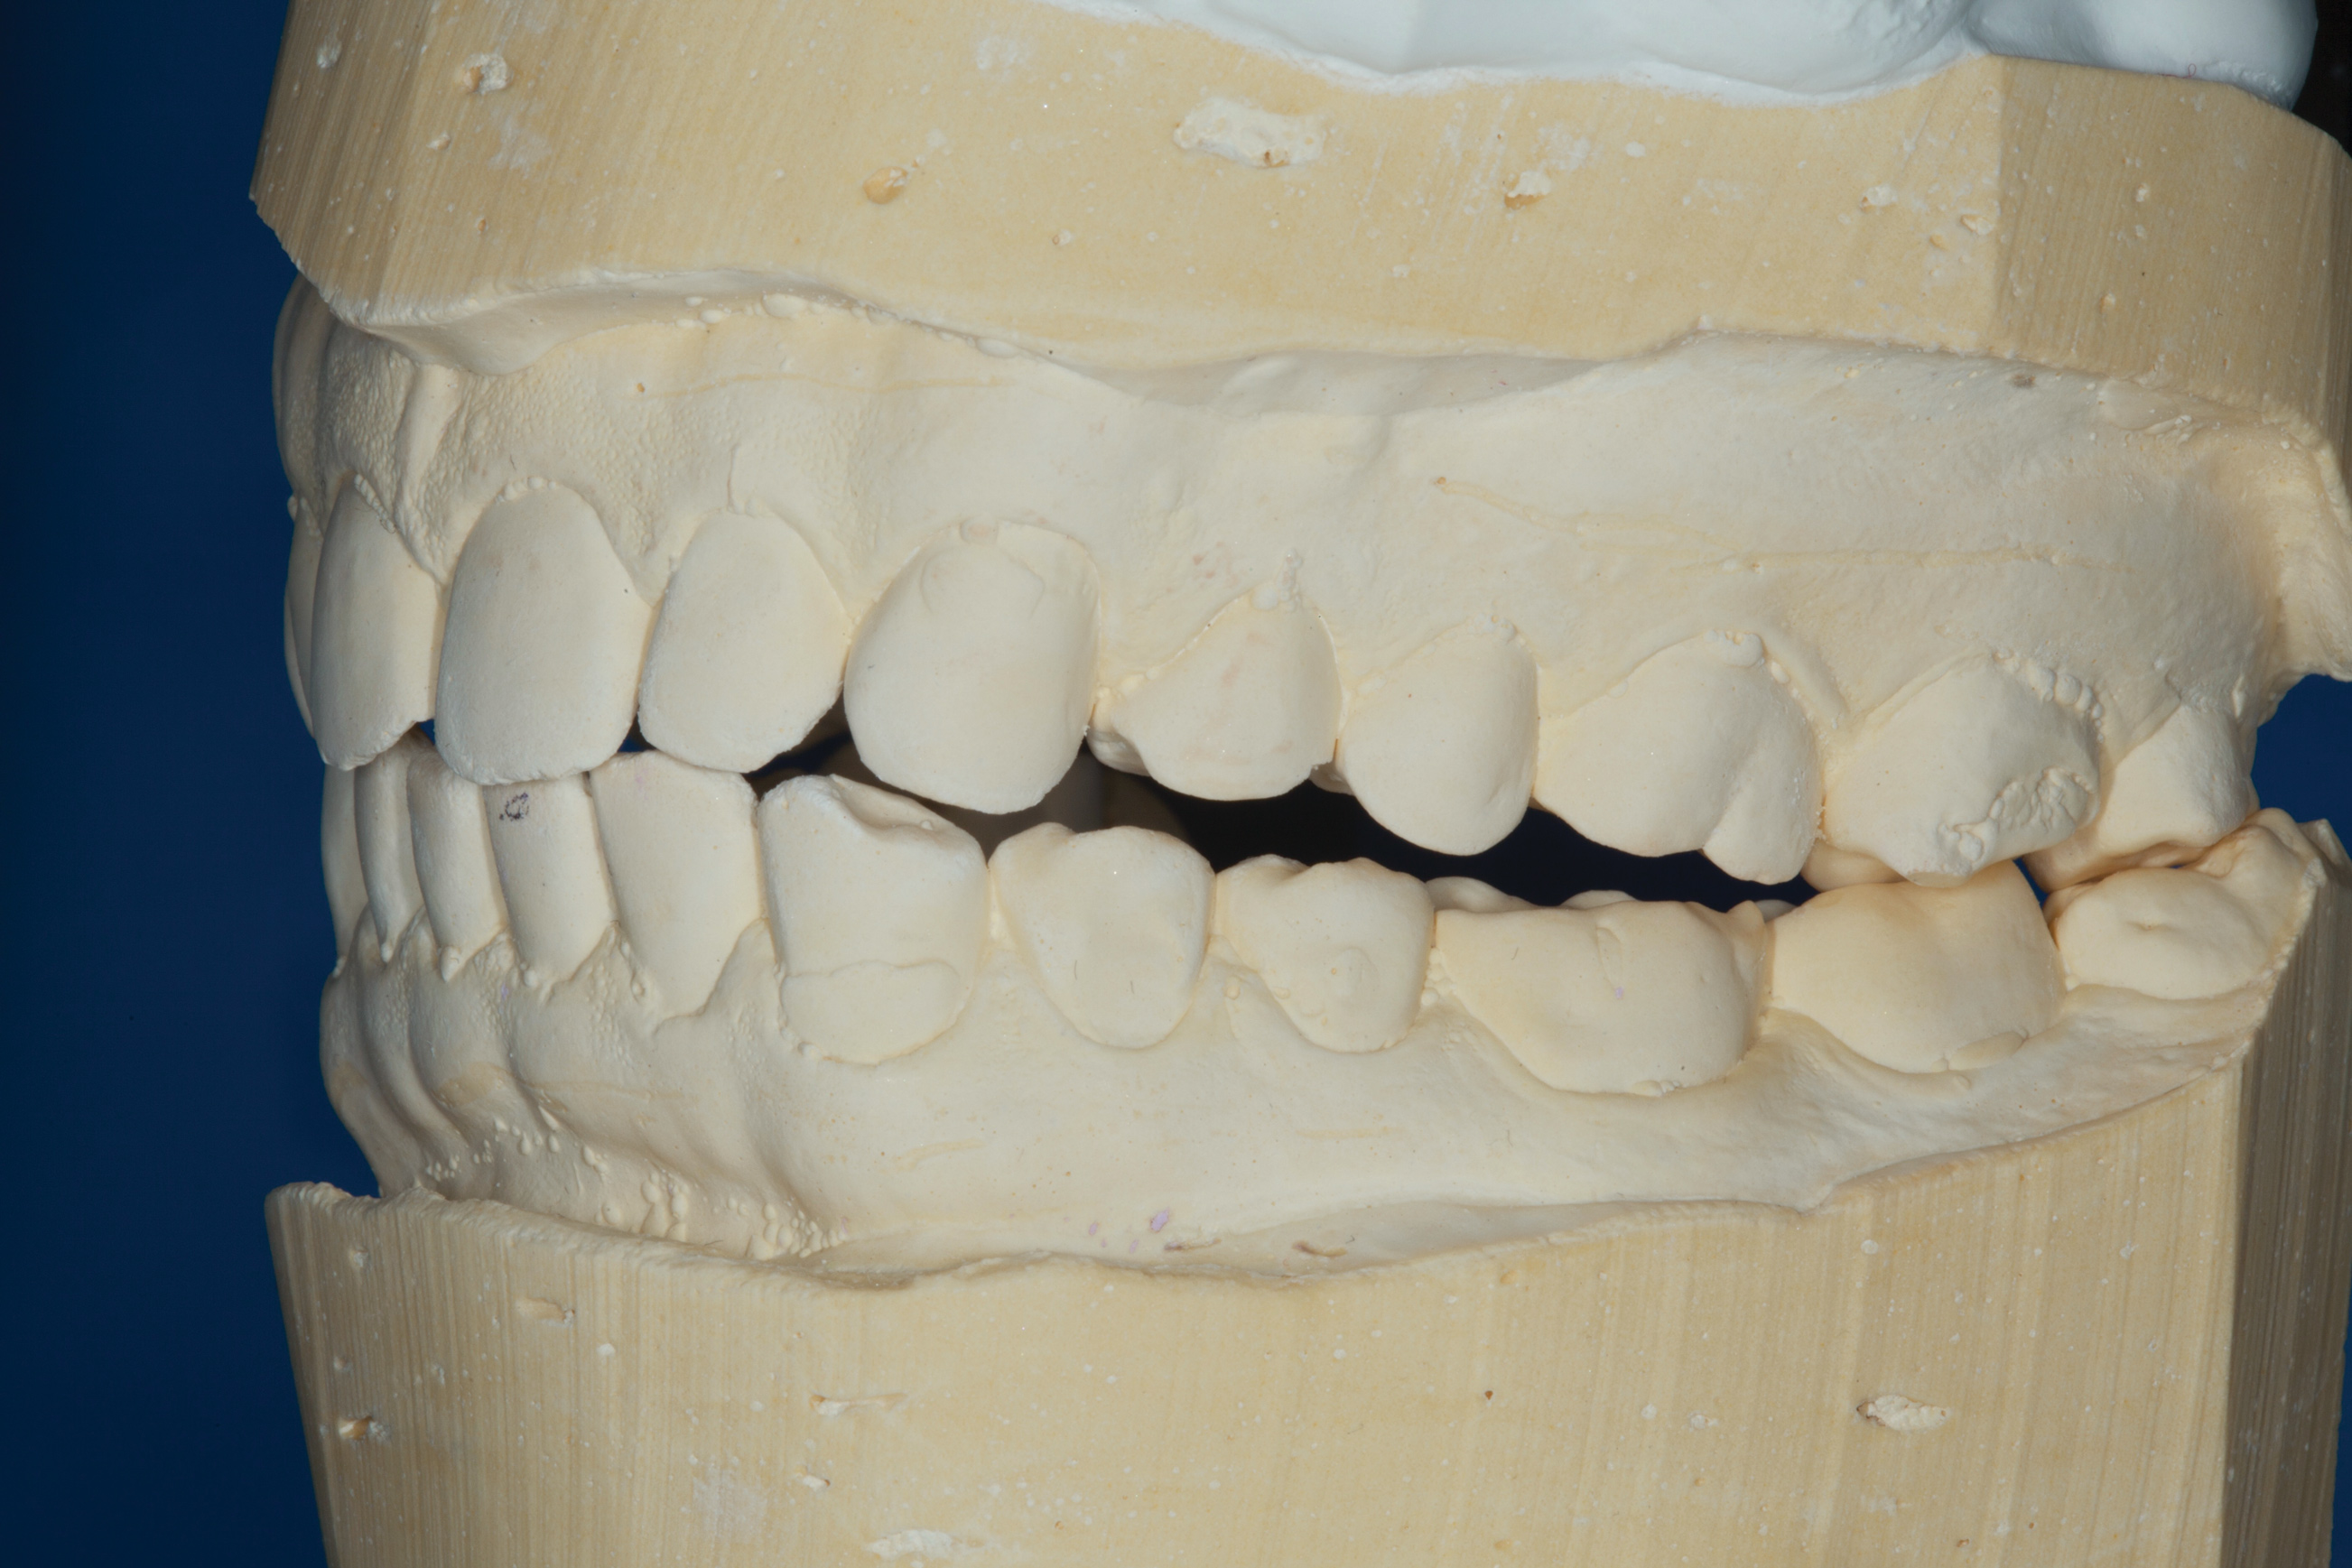

(5.) Mounted models showing maximum intercuspation.

Figure 5

The patient's bite was obviously unsatisfactory, but with the orthotic in place, he was completely symptom-free and stable, and therefore, considered to be in acceptable function. However, he was considered to be in occlusal dysfunction without it because he lacked simultaneous, equal intensity posterior contacts. Deprogramming the patient and confirming centric relation was not considered to be required at this stage because as soon as he removed the orthotic, his occlusal situation was similar to wearing a tripod deprogrammer with only one anterior and two posterior contacts, and these had been confirmed to be reproducible every time when checked intraorally and on the mounted models (Figure 5). The use of a Kois Deprogrammer is one way to obtain centric relation, but other ways, such as bimanual manipulation or the use of a Lucia jig, a leaf gauge, a bite plane, or an occlusal splint have been discussed by various authors.14

Equilibration to close the bite was not possible because the posterior open bite was about 2 mm, which would have necessitated a drastic amount of tooth removal from the second molars. Orthodontic treatment to close the bite was also deemed an inappropriate option because closing the bite would not have eliminated the subsequent need to cover most of the posterior occlusal surfaces with restorations due to the existing erosion. In turn, this would have necessitated removal of tooth structure, which would increase the biomechanical risk of the teeth. Given these factors, the decision was made to close the posterior open bite and create anterior guidance using additive means in the patient's current maximum intercuspation, which was considered equivalent to centric relation. He would then be equilibrated to ensure even, simultaneous posterior contacts and canine guidance.